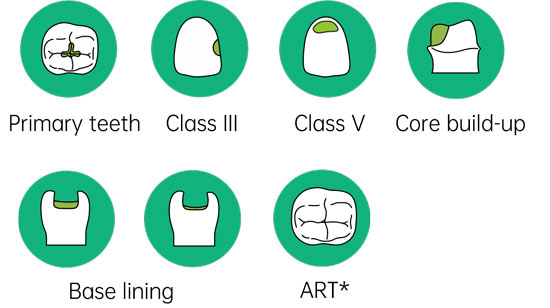

Suitable for a multitude of clinical cases:

Ideal paediatric & geriatric restorative

Restorations of Class III, V and limited Class I cavities.

Provisional or transient restoration

Base linings under composite and amalgam

Core build-up